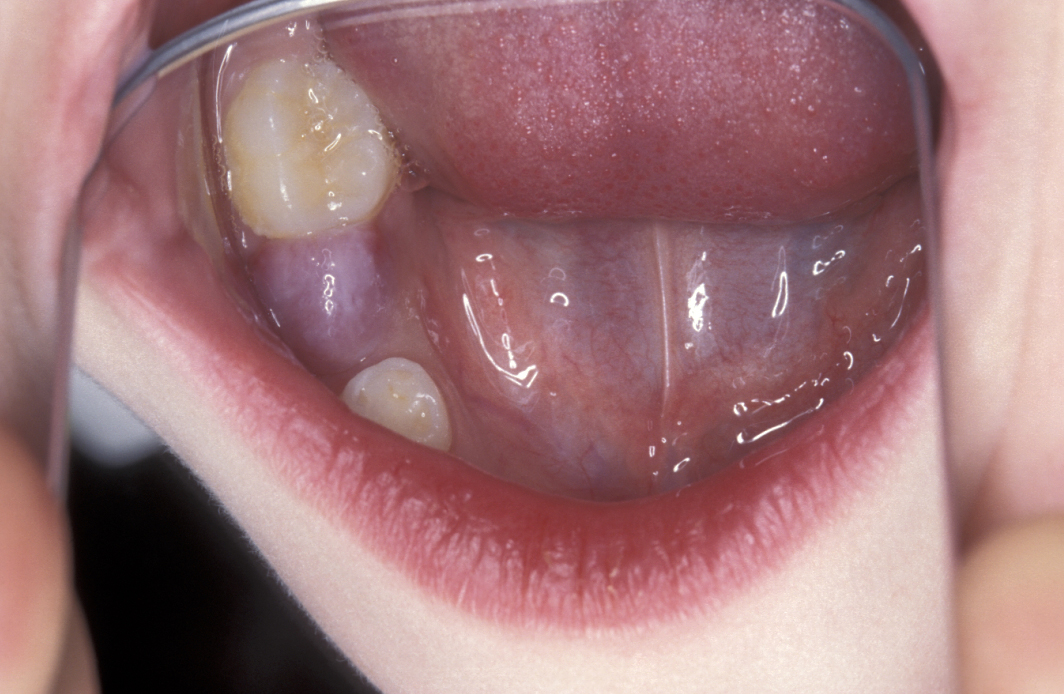

Ranula

Ranulas are mucoceles of the floor of the mouth, usually arising from the sublingual salivary gland or the duct of the sublingual salivary glands. Plunging ranula cross the mylohyoid muscle (below the floor of the mouth) and can appear in the neck.